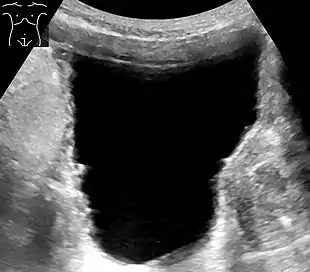

- Ultrasound – sound waves are used to visualize the kidneys and urinary bladder, assess the capacity of the bladder before voiding, and the remaining amount of urine after voiding. This helps know if there's a problem in emptying.